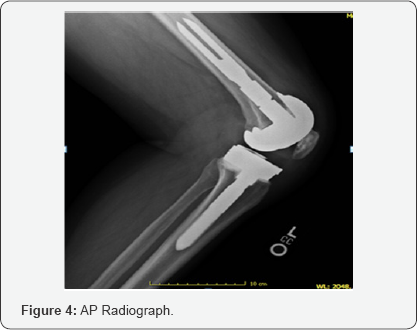

Upon physical examination, it was noted that the patient had a large joint effusion on the left knee and was slightly warm to touch when compared to contralateral knee. The incision site had healed with a supple scar and good cosmesis. Focal tenderness to palpation was noted over medial and lateral femoral condyle. Range of motion was 0-105 degrees measured with a goniometer. The patient had well balanced ligaments throughout arc of motion with appropriate patella tracking and no subsequent subluxation or dislocation. Longstanding lower extremity radiographic evaluation showed 1.3 degree valgus mechanical axis with 91.5 degree medial femoral articular angle and a 90 degree medial tibial articular angle. Radiographs including AP/ Lateral/merchant views showed overhang of lateral aspect of femoral component. Tibial component was well sized. The joint line and patella height appeared within normal limits.

The initial plan was to perform a basic infectious workup with erythrocyte sedimentation rate (ESR) and C-reactive protein (CRP). Knee arthrocentesis was performed and sent for synovial fluid cell count with differential, gram stain, culture and sensitivities, crystal analysis, alpha defensin, synovial CRP and human neutrophil elastase testing. Results revealed an ESR of 60 (normal range 0-22), and a CRP of 1.03 (<.8 normal). Cell count with differential was 606 white blood cell counts with 15% segmented neutrophils which decreased the likelihood of prosthetic joint infection. Crystal analysis was negative and final cultures showed no growth. Synovial CRP, alpha defensin and human neutrophil elastase testing were negative or within normal limits. The patient returned three weeks later with knee pain out of proportion to what would be expected for oversized or malpositioned components. ESR and CRP were again repeated with similar results. A metal allergy serum assay was ordered to rule out metal hypersensitivity. One month later, the results of the metal allergy testing did show reactivity to nickel. The patient elected to proceed with TKA revision with oxidized zirconium (Oxinium, Smith & Nephew) hypoallergenic components. (Figures 1-4) Postoperative lower extremity radiographs.

On subsequent postoperative visits, patient progressed well and was ambulating with a cane by 8 weeks. His pain was overall improved and he had an arc of motion of had 0-110 degrees of flexion. The knee was stable to varus and valgus stress. At 20 weeks postoperative, the patient continued to progress well. Passive range of motion was 0-110 degrees and full strength in quadriceps and hamstring was noted. Radiographs showed overall well sized and well positioned components.